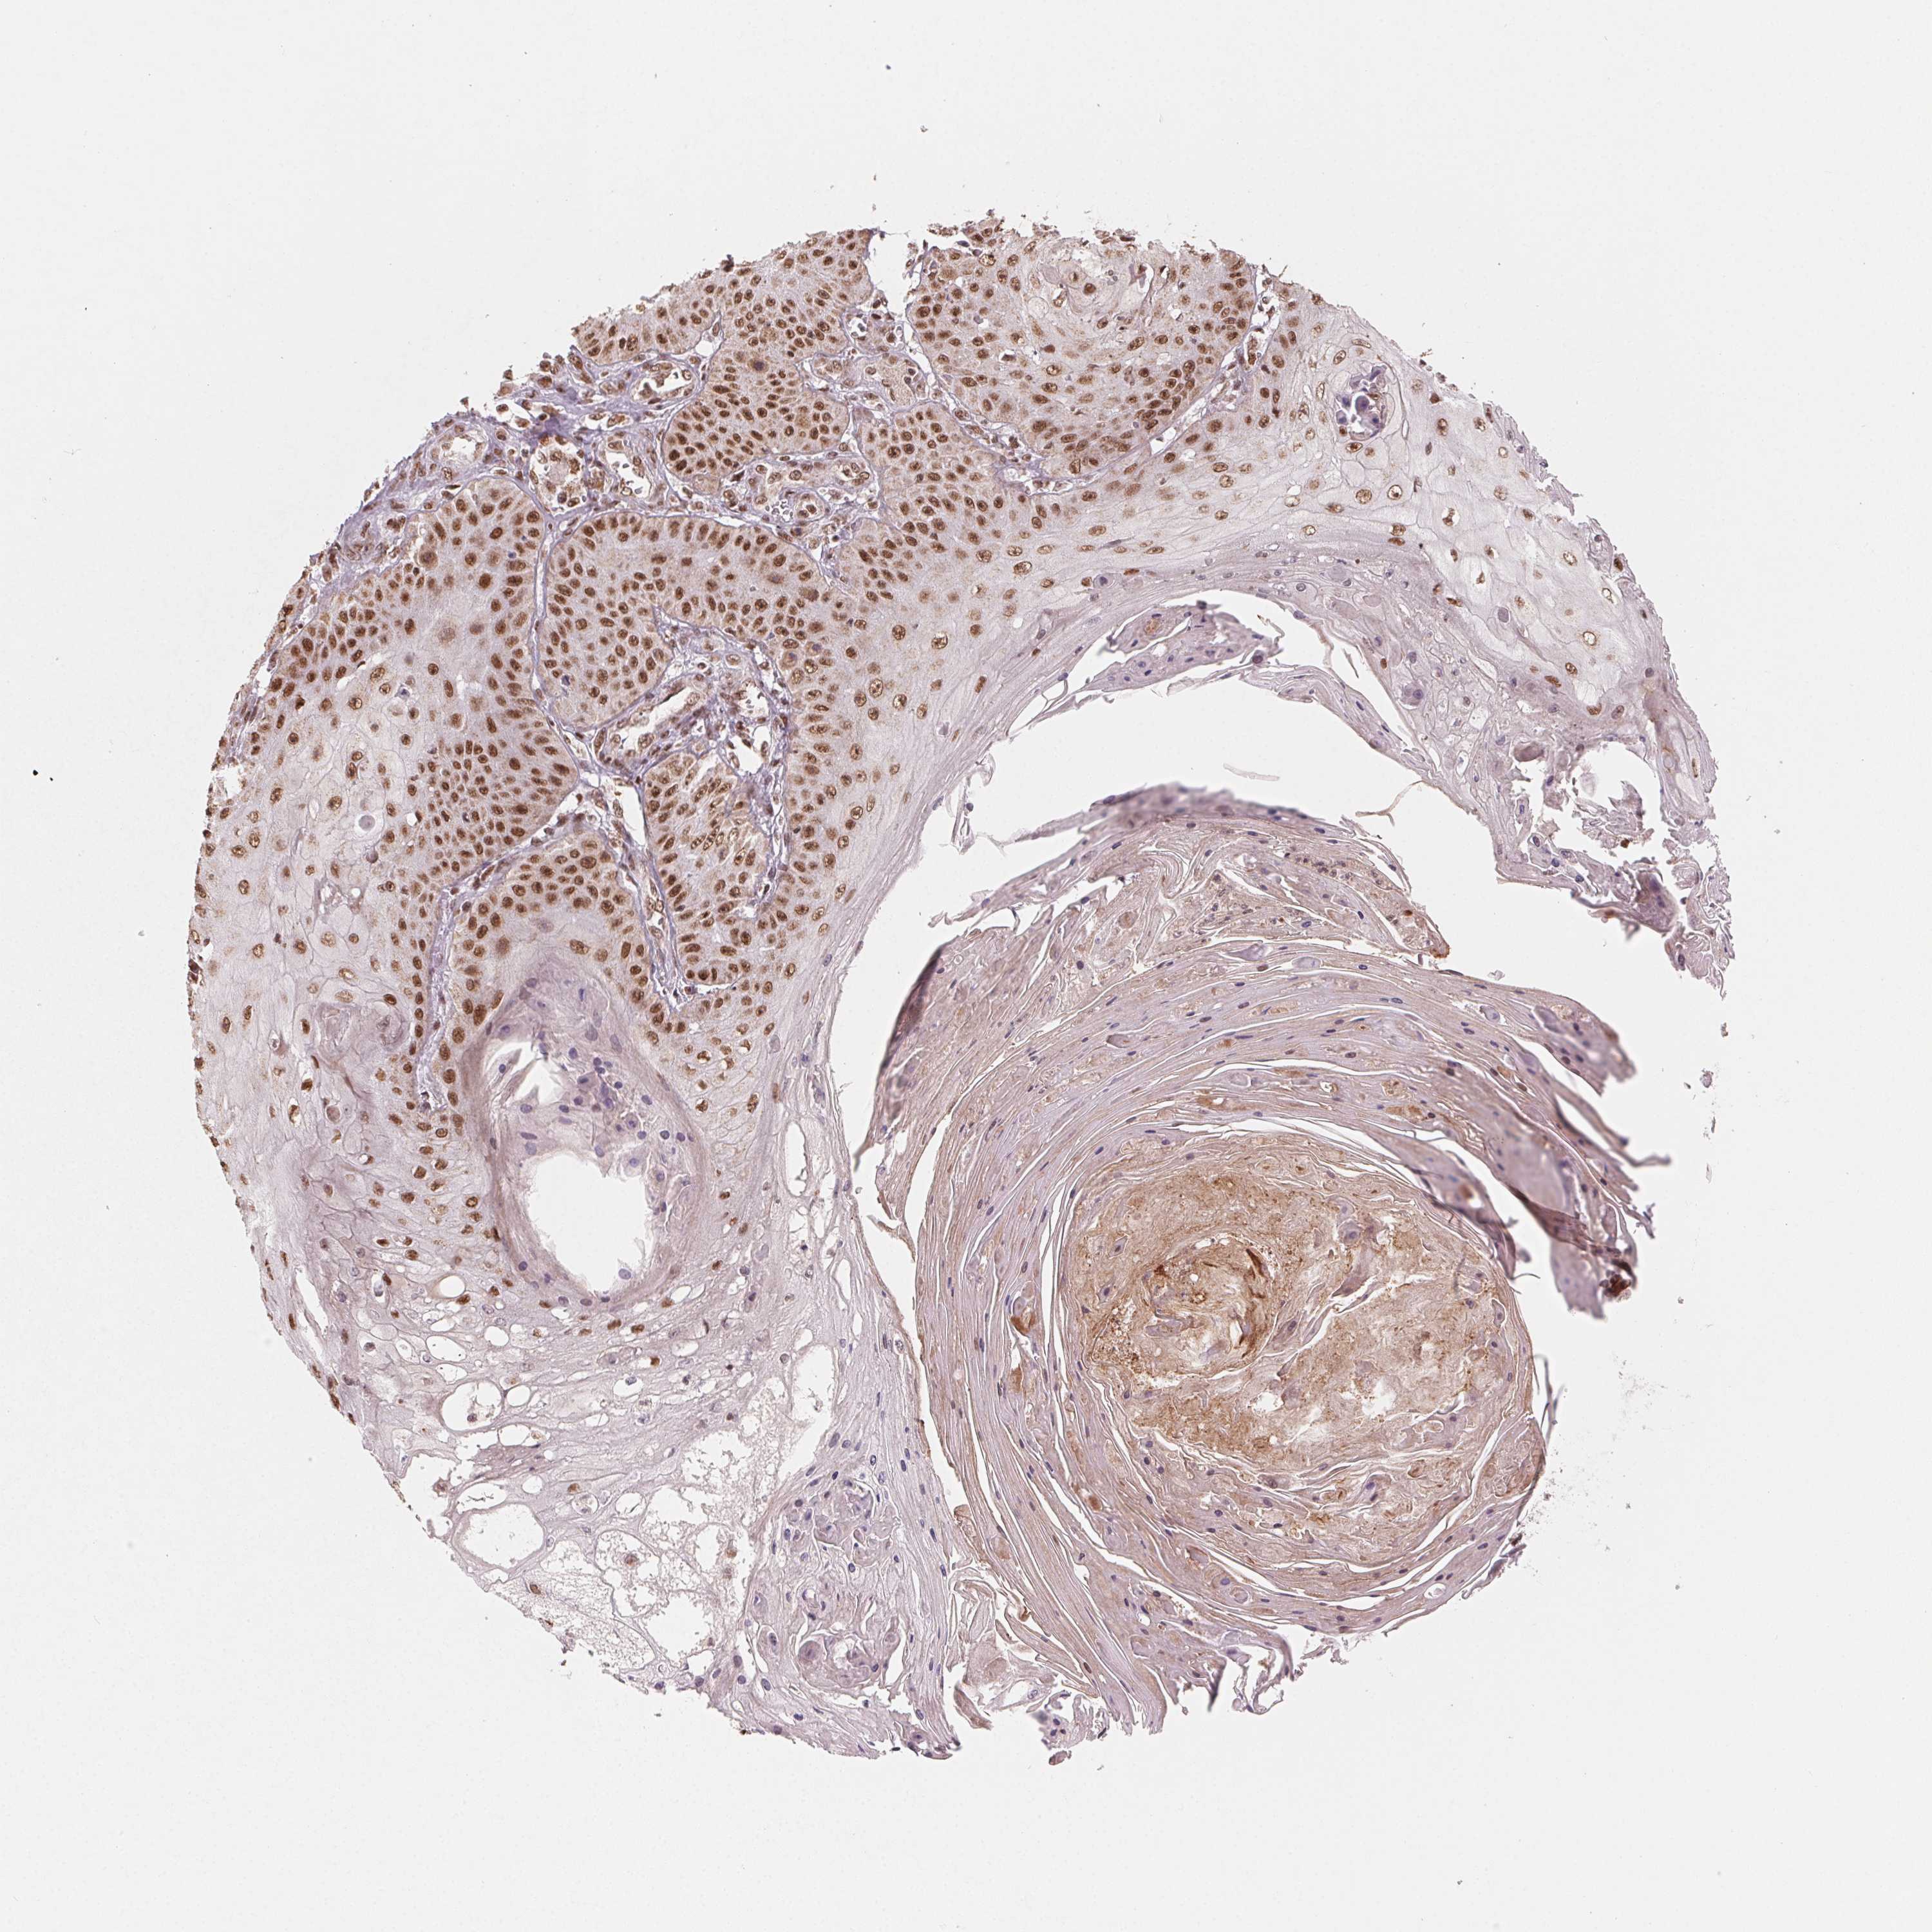

SKIN CANCER - Protein expressioni

A mouse-over function shows sample information and annotation data. Click on an image to view it in a full screen mode. Samples can be filtered based on level of antibody staining by selecting one or several of the following categories: high, medium, low and not detected. The assay and annotation is described here.

Antibody stainingi

Antibody staining in the annotated cell types in the current human tissue is reported as not detected, low, medium, or high, based on conventional immunohistochemistry profiling in selected tissues. This score is based on the combination of the staining intensity and fraction of stained cells.

Each image is clickable and will lead to virtual microscopy that enables deeper exploration of all samples and also displays staining intensity scores, fraction scores and subcellular localization as well as patient and tissue information for each sample.

Antibody HPA065661

Staining

High

Medium

Low

Not detected

Intensity

Strong

Moderate

Weak

Negative

Quantity

>75%

75%-25%

<25%

None

Location

Nuclear

Cytoplasmic/membranous

Cytoplasmic/membranous,nuclear

Basal cell carcinoma

Squamous cell carcinoma, NOS